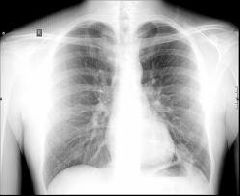

A Organização das Nações Unidas (ONU) advertiu a comunidade internacional que é necessário ampliar os esforços para diagnosticar e tratar cerca de 2 milhões de pessoas no mundo que, de 2011 a 2015, poderão ter tuberculose multirresistente a tratamentos convencionais, chamada de MDR-TB, na sigla em inglês para Multi-Drug-Resistant.

A tuberculose MDR não responde aos medicamentos usados no tratamento convencional da doença e, se não for controlada a tempo, aumenta o risco de propagação, segundo a Organização Mundial de Saúde (OMS) e o Fundo Global de Luta contra Aids, Tuberculose e Malária.

Em 2008, 440 mil casos de tuberculose multirresistente foram registrados e 150 mil pessoas morreram. Na véspera do Dia Mundial da Tuberculose, a ONU apelou para os líderes mundiais que redobrem os esforços para diagnosticar e tratar a doença.

Em 2009, 9,4 milhões de pessoas foram diagnosticadas com tuberculose e 1,7 milhão morreram, incluindo 380 mil pessoas que eram portadoras do vírus HIV. O Brasil integra o grupo dos 22 países em desenvolvimento que concentram 80% dos casos mundiais da doença. Por ano, são notificados cerca de 72 mil casos e de 5 mil mortes por tuberculose.